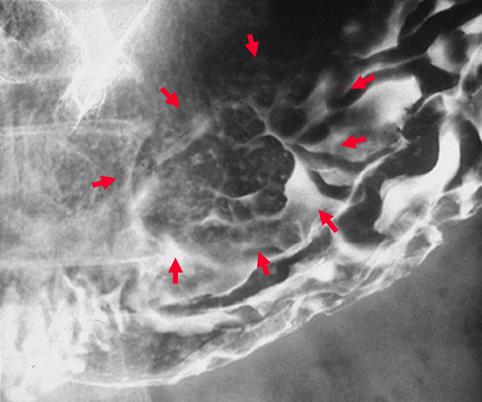

疾病(病理主体)的分类恶性淋巴系肿瘤/恶性淋巴瘤

部位(按器官分)胃(部位)/体部

检查方法X线

肿瘤最大直径40以上

肿瘤的深度sm